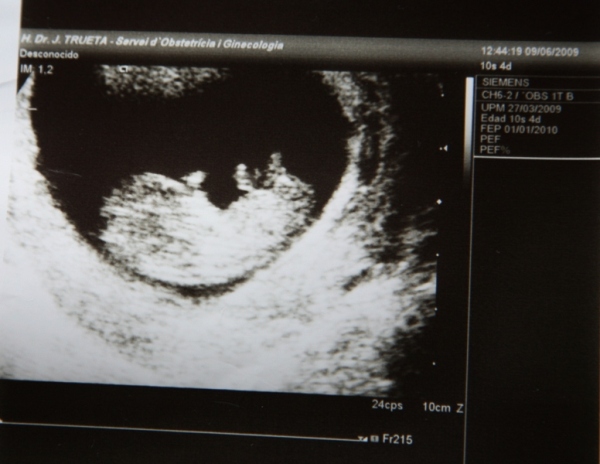

Bogaracska: Grtula a 12. heti UH-hoz!

. Én is úgy döntöttem, hogy jövő hét hétfőn elmegyek a dokimhoz UH-ra, nézzen rá, hogy minden rendben van-e vele. Csak paranya vagyok én most is